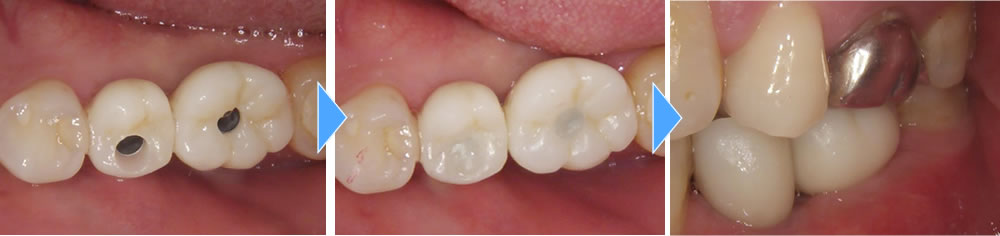

上部構造の装着・治療完了

製作した上部構造を装着し、最終的な咬み合わせを調整して治療完了となりました。骨造成を行ったため、インプラントも骨としっかりと定着し、硬いものも問題なく噛むことができるようになりました。